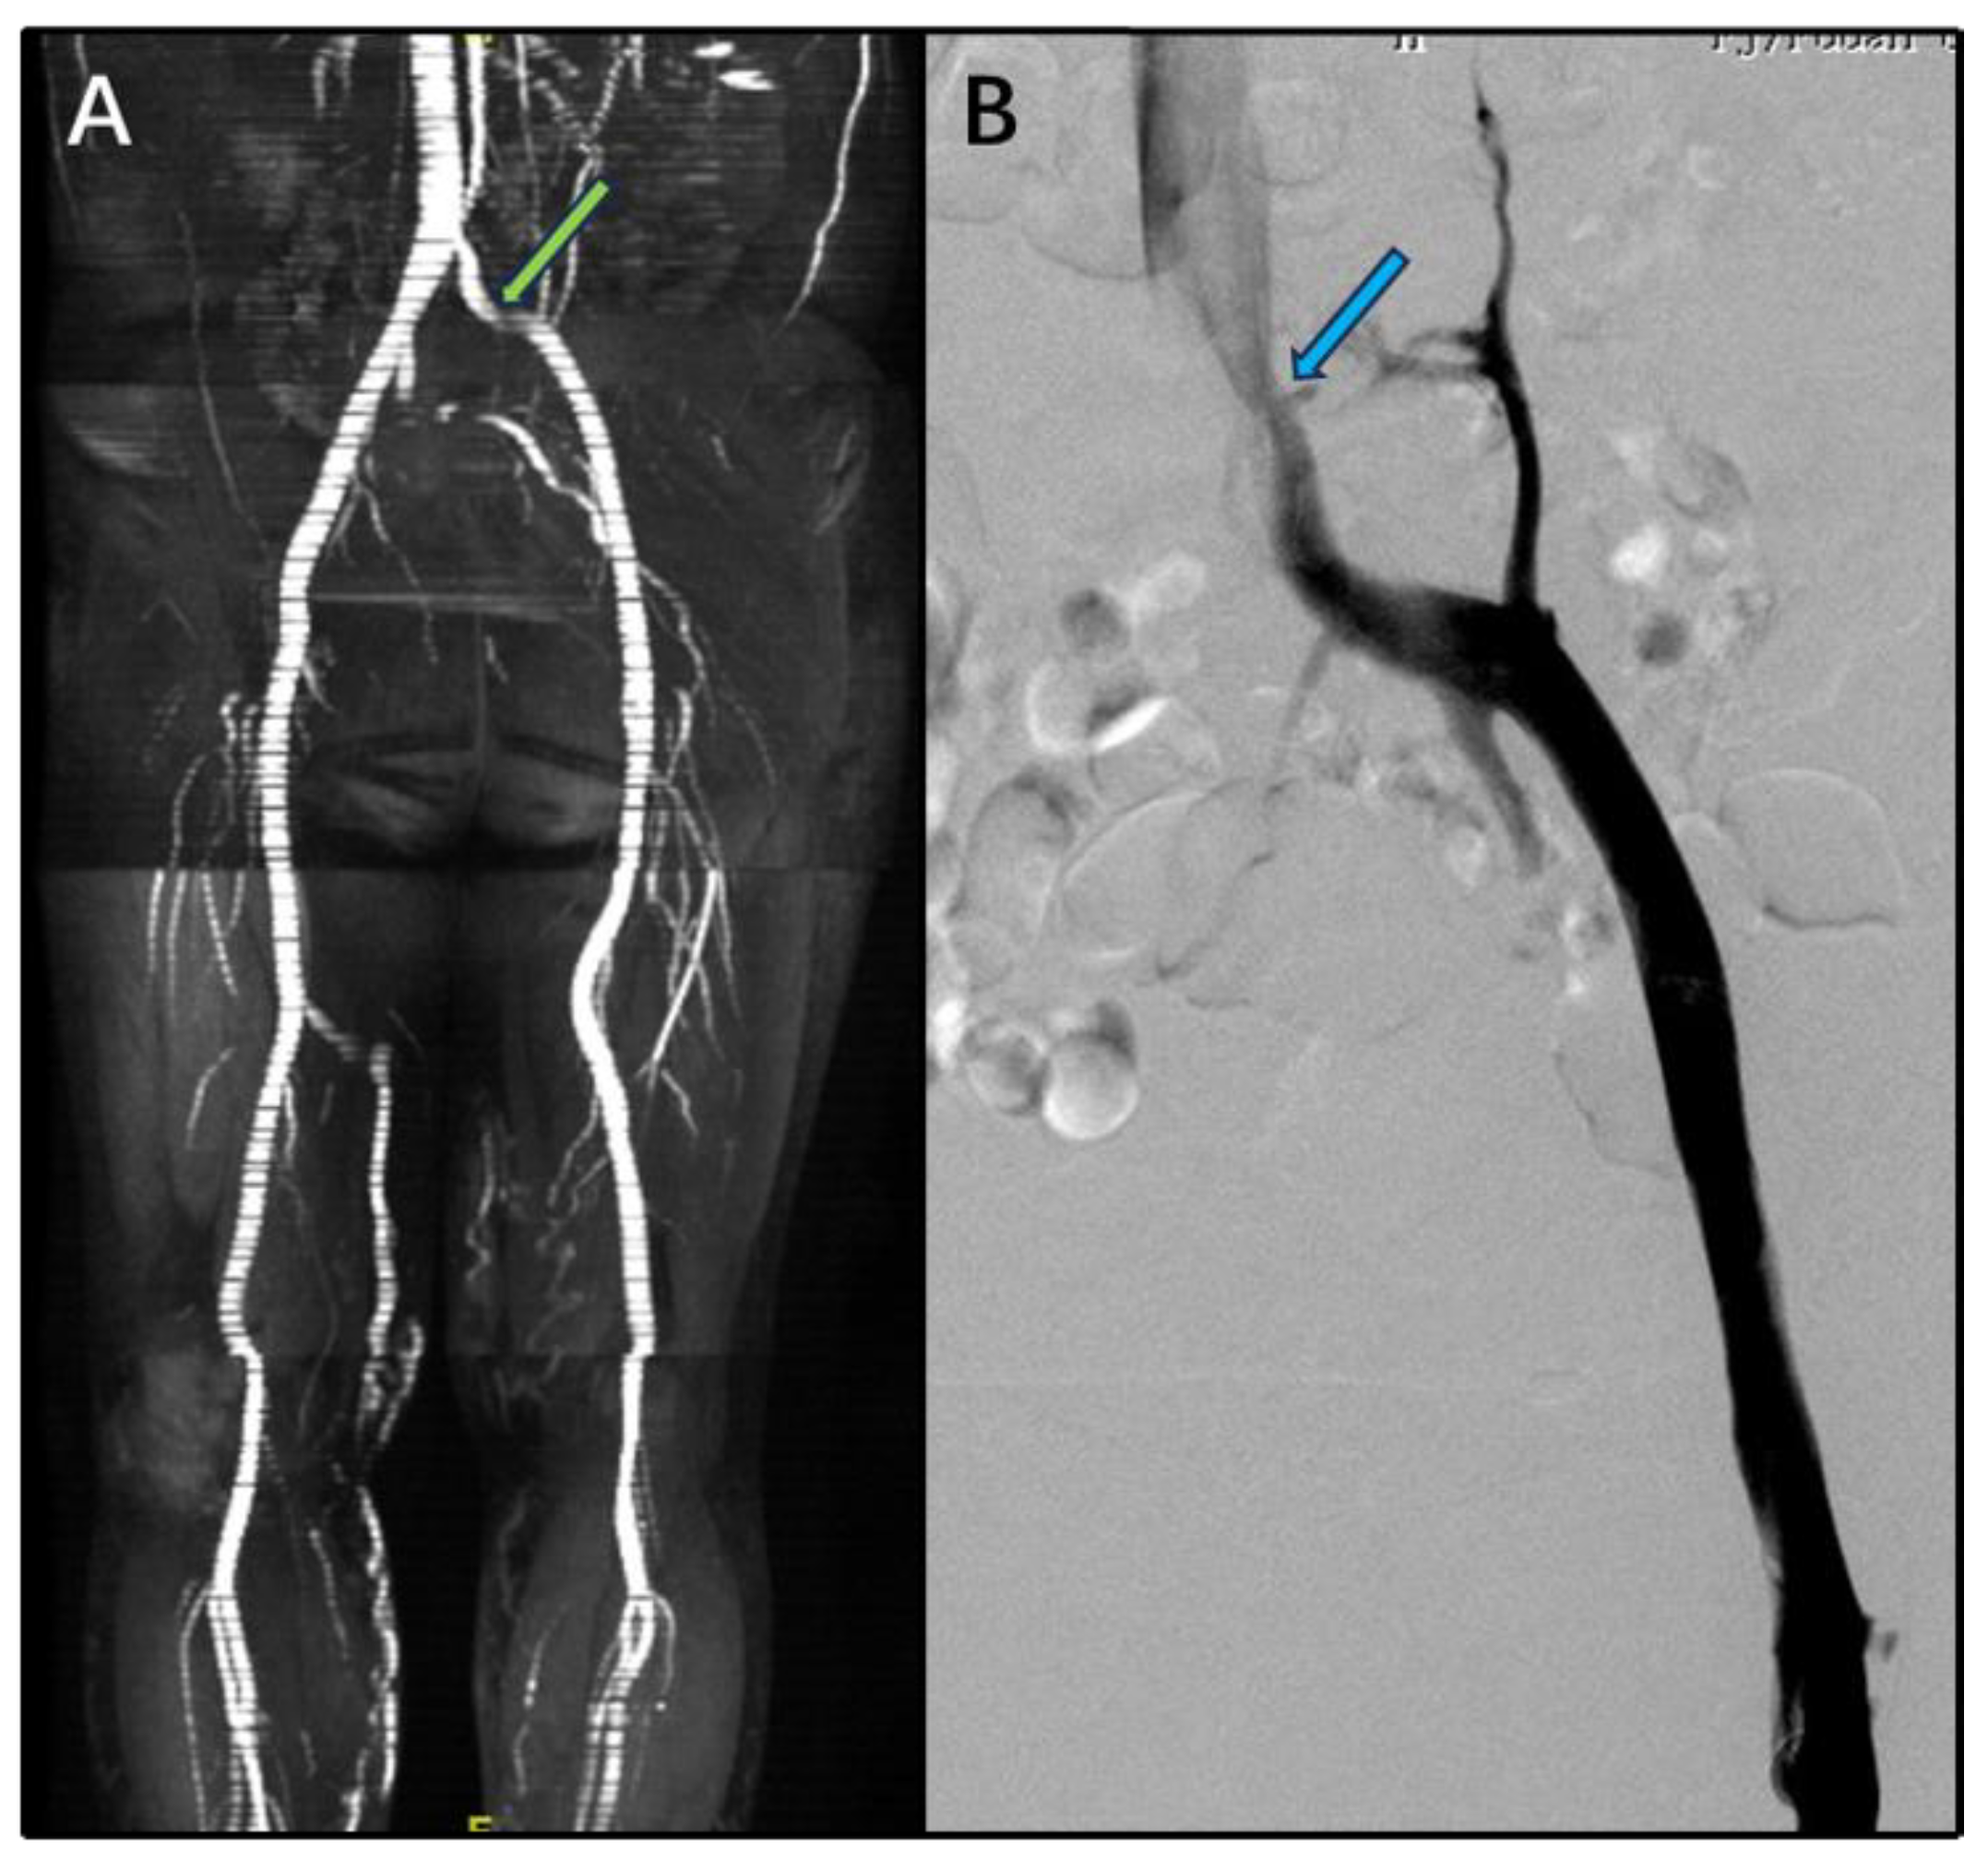

Background/Objectives: Rates of postoperative recurrence of varicose veins range from 7% to 62%. We analyzed factors associated with recurrent varicose veins (RVVs) of the lower extremities after interventional treatment. Methods: We enrolled 99 patients (114 lower extremities) with RVVs admitted from January 2018 to June 2025 (71 women, 76 limbs; 28 men, 31 limbs; average age (SD) 63.9 (9.8) years). Duplex ultrasound scanning, magnetic resonance venography, or computed tomography venography were performed. The presence of a residual great saphenous vein, primary deep venous valve insufficiency, incompetent perforating veins, and iliac vein stenosis were recorded. We analyzed the charts of patients who underwent operations for recurrent varicose veins for associated factors. Results: We recorded residual trunk of the great saphenous vein in 55 limbs (48.3%), deep venous valve insufficiency in 47 (41.2%), incompetent perforating veins in 7 (6.1%), anterior accessory saphenous vein insufficiency in 2 (1.8%), and small saphenous vein insufficiency in 2 (1.8%). Iliofemoral venography indicated 31 limbs (27.2%; left lower, 24; right lower, 7) with a nonthrombotic iliac vein compression lesion. After identifying associated factors, retreatments—high ligation and stripping of the great saphenous vein or iliac vein stent implantation or small saphenous vein dissection ligation and stripping—were performed. The venous clinical severity score was 7 (interquartile range, 5–10) on admission and 3 (interquartile range, 2–4) 3 months after discharge.Conclusions: RVVs are associated with multiple factors, including inadequate initial surgical techniques, nonthrombotic iliac vein compression lesions, deep venous valve insufficiency, small saphenous vein insufficiency, and incompetent perforating veins. Performing detailed imaging before retreatment is essential to identify factors associated with RVVs and prevent recurrence.